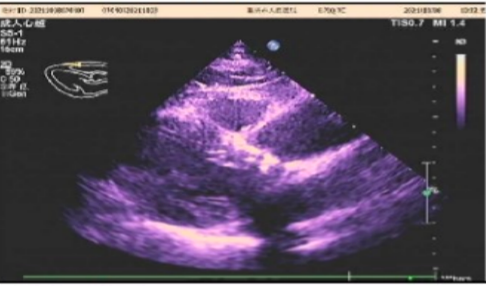

心脏彩超

主动脉瓣病变:主动脉瓣重度狭窄伴大量反流

峰值流速:4.8m/s;

平均跨瓣压差:53mmHg;

左室射血分数EF值:56%;

左室舒张末期内径(LVD):54mm;

左房增大,主动脉增宽,二尖瓣少量返流,左室舒张功能减退。